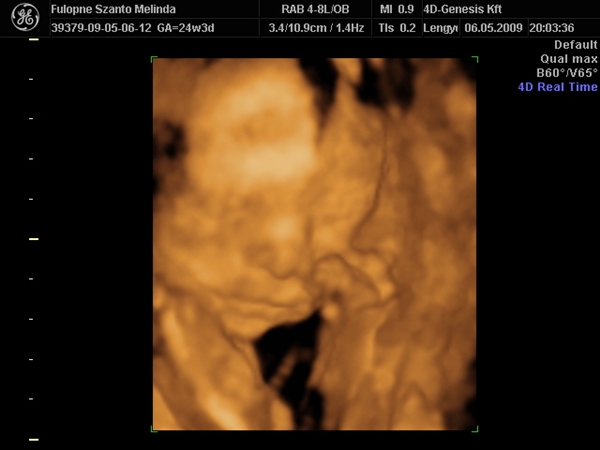

Na rakok képet,Budán voltunk a 4d genesis,de megmutatom,van honlapja.... Kép Kép Kép Kép Kép

Szóval!Nagyon csodálatos volt látni (nekem újra) a picúrt! :lol:

Mint ahogy kiderült,nem is olyan picúr!Ma vagyok 15 hét 2 napos,a bab méretei meg 16 hetesnek felel meg.Persze tudom,ez még változhat.Szegénykém olyan furi pózt vett fel,de hát ha neki úgy kényelmes,legyen úgy! :lol: :lol: :lol: :wink: Úgy képzeljétek el,mint a fordított C betű.Lent van a feje,felfelé áll a törzse és balra fordulva a lábai.Nem tudom elég érthető volt e így,de sajna jobban nem tudom elmagyarázni.

A méretei:

BPD:3,6 cm

OFD:4,4 cm

HC:12,85 cm

FL:1,96 cm

AC:9,69 cm

CRL:9,83 cm

A szivecskéje is nagyon vert,olyan jó volt hallani,láttam párom is belekönnyzett! :shock: :lol:

És végül úgy néz ki,90 % hogy KISFIÚ!!!!!!